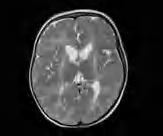

Leukodystrofie hipomielinizacyjne (LH) 7, 8, 11 oraz 21 (POLR-related hypomyelinating leukodystrophy) są związane z autosomalnymi recesywnymi mutacjami w genach polimeraz RNA, odpowiednio w genach POLR3A, POLR3B, POLR1C oraz POLR3K. Są to niezwykle rzadkie choroby, mogące występować w postaciach pełnoobjawowych oraz poronnych. W postaci pełnoobjawowej, oprócz rozległej hipomielinizacji mózgowia w badaniu RM (ryc. 5.2), stwierdza

się niekiedy hipodoncję/oligodoncję (brak zawiązków niektórych zębów) oraz hipogonadyzm hipogonadotropowy, stąd postać ta nosi nazwę zespołu 4H. U tych chorych nie pojawiają się samoistnie cechy dojrzewania płciowego. Niekiedy są niscy wskutek niedoboru hormonu wzrostu. Objawy te mogą zmylić lekarza – może on podejrzewać, że ma do czynienia wyłącznie z wielohormonalną niedoczynnością przysadki lub zespołem Turnera. Ząbkowanie jest niekiedy opóźnione, brak jest niektórych zawiązków zębów mlecznych i stałych. Sporadycznie opisywano ząbkowanie noworodkowe. Przebieg LH7/8 jest najczęściej powolny i postępujący. Z reguły, im wcześniej choroba się ujawni, tym cięższa jest jej postać. W pełnoobjawowym zespole 4H najczęściej obserwuje się opóźnienie rozwoju ruchowego, niezgrabność ruchową, uogólnioną wiotkość oraz powoli postępującą ataksję. W zależności od postaci choroby dochodzi do narastania zaburzeń neurologicznych i regresu umysłowego lub otępienia. W postaciach o początku w wieku wczesnodziecięcym przebieg jest postępujący i do zgonu dochodzi w pierwszej dekadzie życia. Im późniejszy wiek ujawnienia, tym przebieg jest w miarę stacjonarny. Rozwój umysłowy może być prawidłowy. Chorzy mogą wykazywać jedynie różnego stopnia niezgrabność ruchową. Ze względu na zmiany w osłonkach nerwów obwodowych odruchy głębokie są osłabione, a objaw Babińskiego występuje dopiero po latach. W diagnostyce klinicznej pomocne jest wykonanie pantomogramu ujawniającego hipodoncję. Rozpoznanie potwierdza badanie genetyczne. Leczenia przyczynowego nie ma, wskazana jest rehabilitacja ruchowa, przy niedoborach hormonalnych konieczne jest leczenie hormonalne. Ryzyko dla potomstwa rodziców, nosicieli mutacji, wynosi 25%.

Rycina 5.2. Leukodystrofia z hipomielinizacją, hipodoncją, hipogonadyzmem hipogonadotropowym (zespół 4H) u 17-letniej chorej. Hiperintensywność całej istoty białej oraz jej zmniejszona objętość wskutek braku mielinizacji, w tym niezmielinizowane torebki wewnętrzne oraz nieco poszerzone komory boczne. RM T2-zależny.